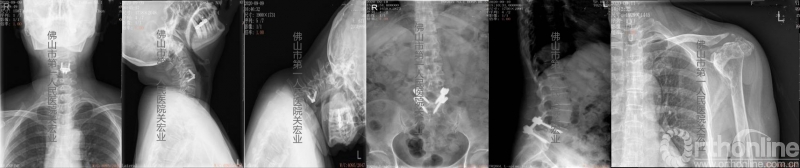

影像学检查:

术前放射检查

术前CT

术前CTA

术前MR

诊断:

1.类风湿性关节炎

2.寰枢椎半脱位

3.颈椎术后

4.腰椎滑脱术后

5.左足、左肩类风湿性改变

6.糖尿病